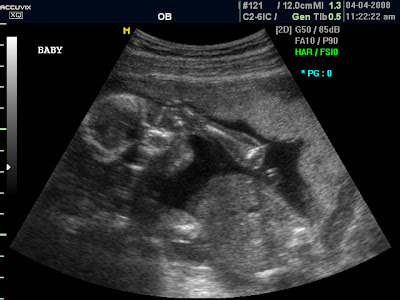

Wow, I can't believe I'm sharing moving images of the tiny fetus growing in my belly with the entire world. That's weird.

Ultrasound

Well, just as I was tearing up and preparing to wait another four weeks to find out the gender, the tech got the money shot. Clark saw it right away and then the two of them tried in vain to show me how obvious it was. I'll have to take their word.

She wasn't able to see everything (the heart and spine weren't too clear) so I get to come back in 4 weeks without the burden of not knowing the gender. Its ideal. I LOVE ultrasounds, especially when everything looks normal and healthy, and they can tell without a doubt that we're having a...